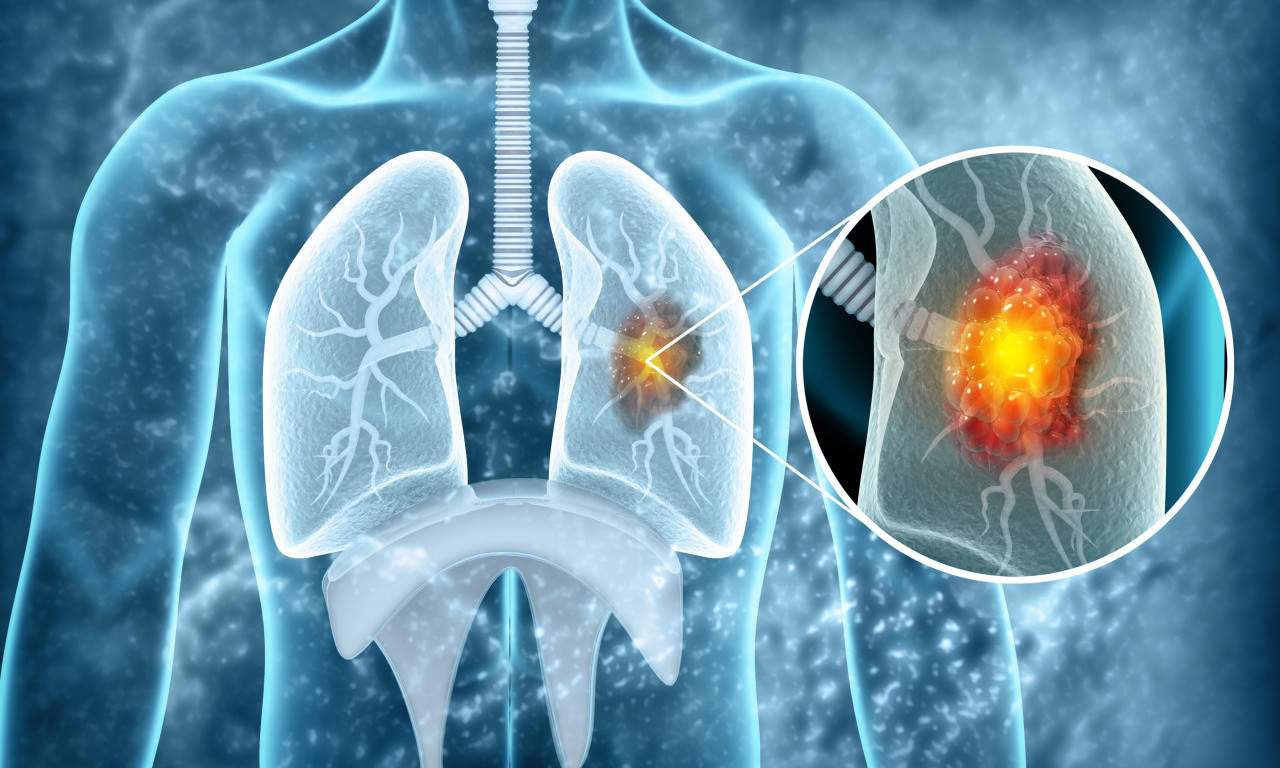

rak pluća

VEŠTAČKA INTELIGENCIJA OTKRIVA RAK PLUĆA MESEC DANA UNAPRED! Potrebno je uraditi osnovne medicinske analize

Na svaka dva sata u Srbiji jedna osoba premine od KARCINOMA PLUĆA! Od jeseni počinje "borba" u SRBIJI, a evo i kako

Svetski dan borbe protiv raka pluća obeležava se svake godine 1. avgusta.

Rak pluća je vodeći uzrok smrti od raka u svetu, a godišnje ima 1,8 miliona smrtnih slučajeva od kancera pluća

ALARMANTNI PODACI U SRBIJI! Od RAKA PLUĆA oboli 7.000 SRBA godišnje, što nas stavlja na drugo mesto u Evropi

CRNA STATISTIKA: 70% obolelih RAK PLUĆA otkrije tek kad su ŠANSE ZA IZLEČENJE MINIMALNE, ovo je NAJVEĆI PROBLEM

Doktor je objasnio koje metode lečenja postoje u Srbiji i na koji način se određuje da li će pacijent biti podvrgnut inovativnom lečenju

Srbija drži PRVO MESTO u Evropi po smrtnosti od KARCINOMA PLUĆA - zašto je to tako?

Ukoliko se otkrije na vreme, ova opaka bolest je izlečiva